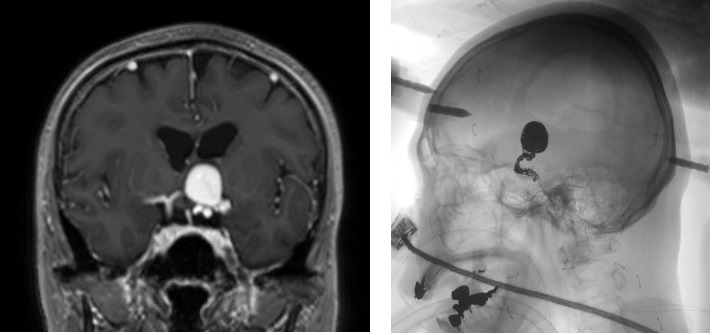

外科的クリッピングと血管内コイリングは、脳動脈瘤の 2 つの主な治療法です。

「クリッピング」は、動脈瘤の頸部に小さなクリップを配置して血流を遮断する観血手術です。一方、「コイリング」は、薄い金属コイルを動脈瘤に挿入して動脈から塞ぐ、低侵襲手術です。

脳動脈瘤の破裂を防ぐために、医師は「血管内コイリング」と呼ばれる低侵襲手術を推奨することがよくあります。

コイリング中に、外科医は小さなワイヤーコイルを動脈瘤に挿入して血流を遮断します。一般に、コイル状にすることはクリッピング (開腹手術) よりも安全ですが、コイル状にすることは、短期記憶と長期記憶の両方を含む特定の機能に影響を与える可能性があります。